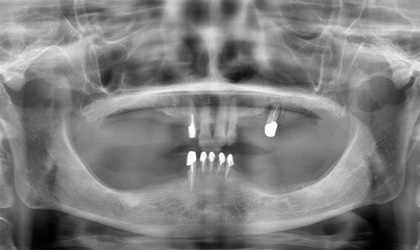

缺牙的處理,一般有兩種方式,一是製作牙橋,另一是放置人工植牙。

放人工牙根,也就是植牙,其最大好處就是不用修磨旁邊的牙齒,這一點其實是無價,而且完成後的咬合功能很好,幾乎和自然牙一樣,但植牙的費用較牙橋高,一顆植牙費用大約是六七萬甚至超過十萬 ( 因案例難易程度 ) ,會因為使用廠牌和有沒有補骨頭而有費用高低之不同,但植牙的使用年限較長,同時可避免周圍的骨頭繼續減少 ; 若照顧良好,也可能好幾十年,一般而言,十年的成功率有百分之八九十,算是非常高;植牙因為要等骨頭和植體長牢,所以需要一些時間,一般上顎的牙要五、六個月,下顎因骨頭較為緻密,所以只需三四個月,但以長期的健康考慮,幾個月其實很快 ; 以專業的建議,植牙確實比較好。

植牙

優點 : 最接近自然牙, 齒槽骨不會再吸收,保護剩餘的牙

缺點 : 費用較高,完成時間較長 ( 但不需一直就診 ) ,需小手術